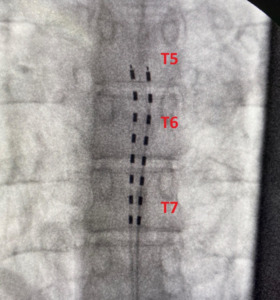

Given the failure of conservative and interventional therapies, the patient was considered for neuromodulation. He underwent a SCS trial utilizing Nalu SCS technology [Nalu Medical, Carlsbad, California], during which leads were placed from the inferior border of T5 into T7, targeting both the thoracic and upper lumbar regions to capture abdominal and back pain. The trial proved successful as the patient reported 75% relief in his overall symptoms. He proceeded with permanent SCS implantation. Six weeks post-recovery, he reported a 70% reduction in axial back pain and 50% reduction in abdominal pain. He experienced improved daily function, increased mobility, and reduced his oxycodone dose to 5 mg three times daily as needed.

While SCS is widely used for conditions such as failed back surgery syndrome and complex regional pain syndrome, its role in visceral pain, such as that from chronic pancreatitis, is still in the initial stages of investigation. The proposed mechanism of SCS in treating visceral pain is to target the postsynaptic dorsal column pathway, making it a major afferent visceral pain pathway.11 Careful lead placement at the T5–T7 levels allowed coverage of both pain regions. Importantly, the patient was able to significantly reduce opioid consumption which is a significant goal in modern pain management.